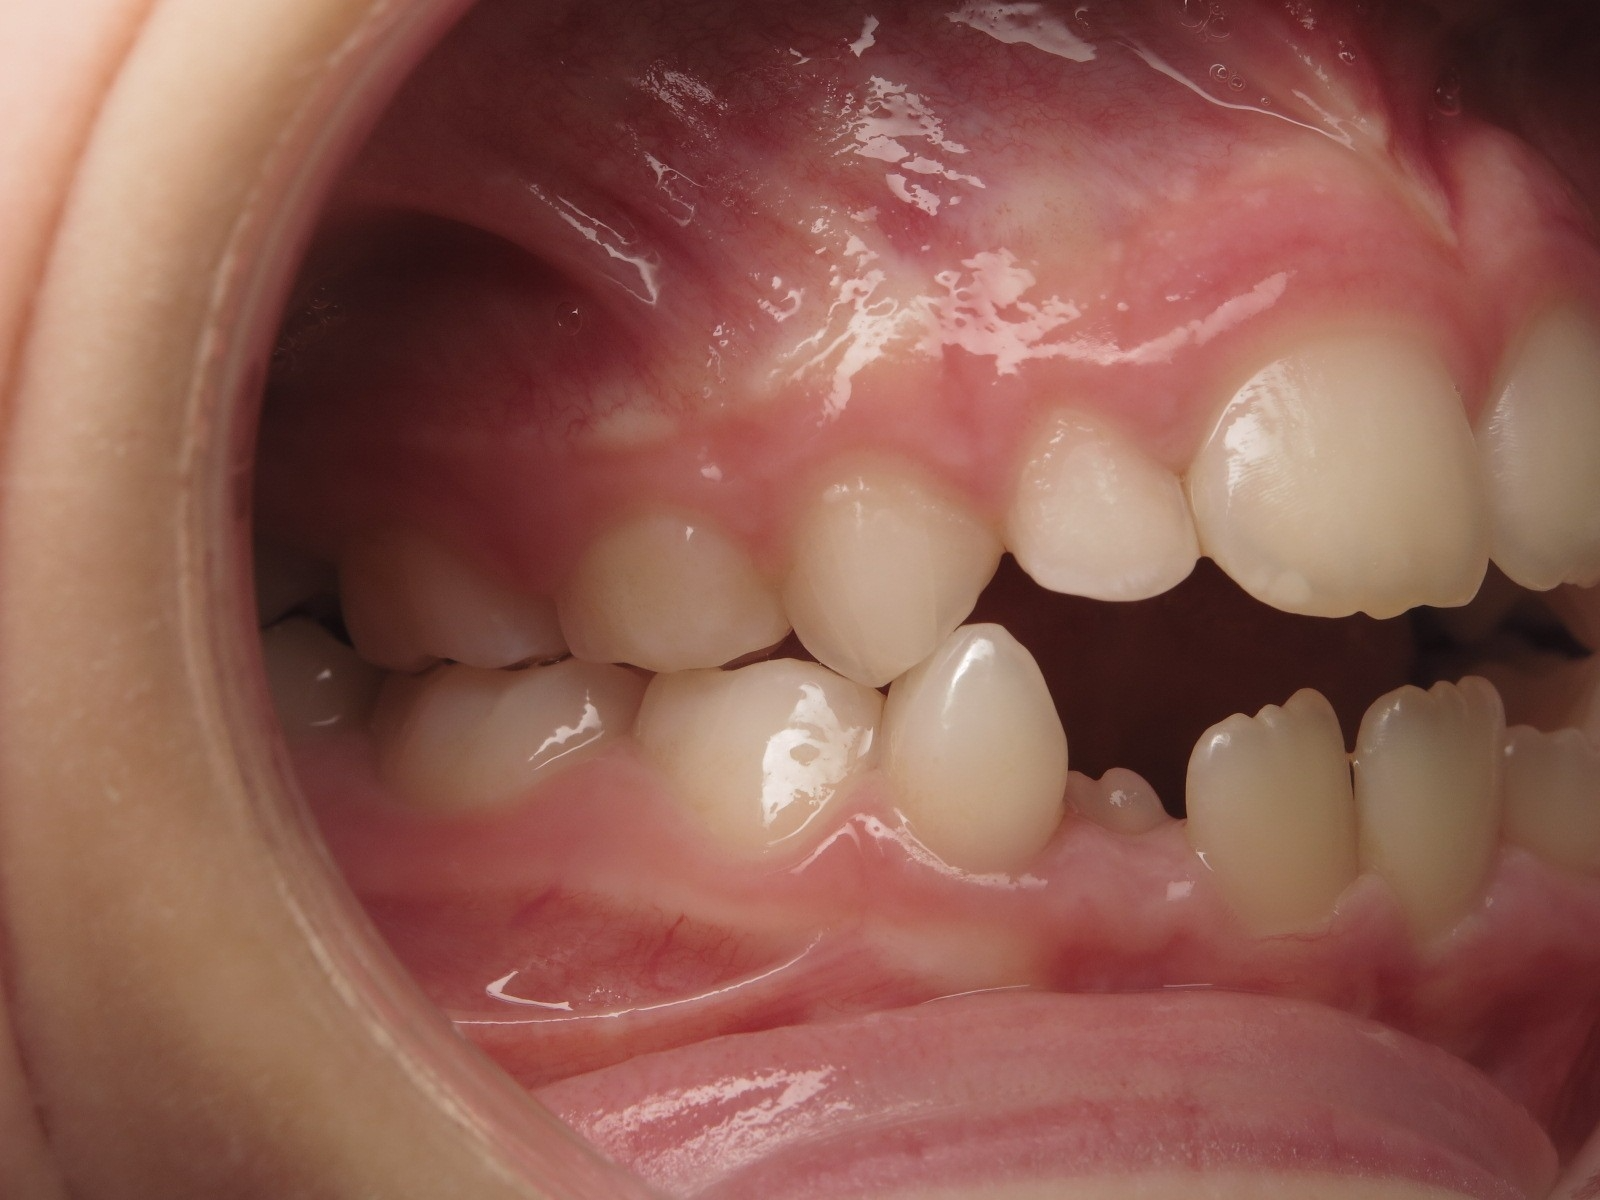

14 béance inversé gauche 5 ans

inversion postérieur coté droit et espace entre l'arcade du haut et du bas (béance)